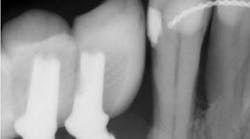

The diagnosis and prevention of peri-implantitis was described in detail in a paper published in the Journal of Periodontology in 2013. It states that peri-implantitis is characterized by inflammation in the tissue surrounding the implant, bleeding on probing (BoP), and radiographic evidence of bone loss exceeding 1.5 mm (due to biologic width formation) and greater than 0.2 mm per year after that. The best treatment is prevention, and it is the responsibility of the hygienist and restorative dentist to examine each implant at maintenance visits. If signs of peri-implantitis exist, early treatment has been shown to prevent further bone loss and restore the implant to health. Radiographs should be taken immediately on the day of restoration and then periodically whenever BoP is evidenced with probing depth increases. Treatment of moderate or advanced peri-implantitis with bone loss up to two-thirds of the implant length has been shown to be successful in restoring lost bone support following a published regenerative procedure (See Froum SJ, et al. Successful management of peri-implantitis with a regenerative approach: a consecutive series of 51 treated implants with 3- to 7.5-year follow-up. Int J Periodontics Restorative Dent. 2012.).